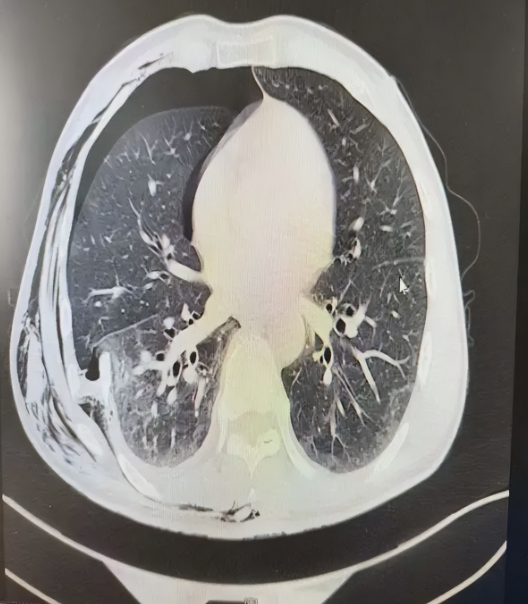

55岁的张先生车祸受伤严重,被紧急送到集团急诊中心救治,经CT检查显示,右侧第4-12肋骨多根多处骨折,右侧气胸、胸腔积液(积血可能),右肺渗出性改变,考虑创伤性湿肺,左肺坠积性改变,气管及左右主支气管痰液潴留,右咽旁、右颈部、胸腰背部、右上肢软组织区广泛积气。查体见连枷胸,反常呼吸,吸氧状态下仍无法维持氧饱和度在正常状态。

术后5天CT复查结果满意,肋骨骨折固定可,肺复张良好。